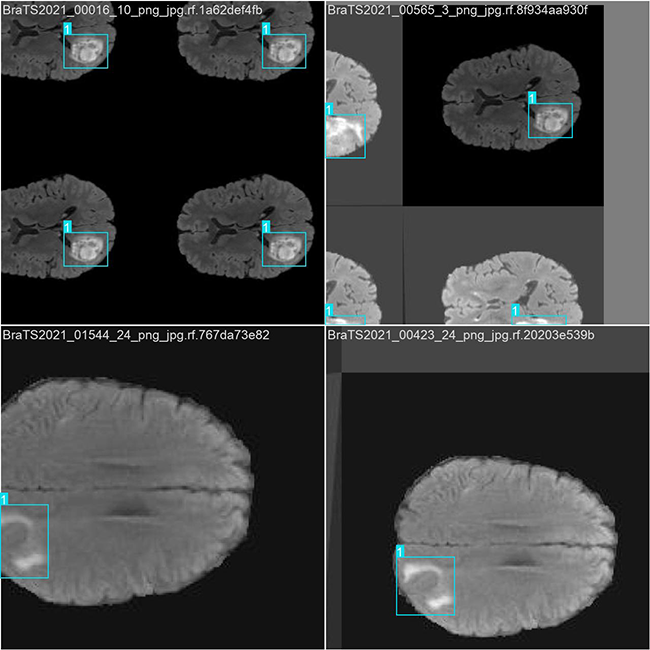

基于YOLO格式的脑肿瘤目标检测数据集

图片数量: 总计共计3841张。该数据集分为训练集2688张、验证集768张以及测试集385张。

类别:2类 [‘无肿瘤’,’肿瘤’]

标签(names): [‘No Tumor’,’Tumor’]

目标检测训练数据可视化

目标检测训练过程中,在处理数据时采用可视化技术进行呈现分析。该系统能够直观呈现复杂的目标特征及其分类标记情况。经过测试分析发现,在整体性能上表现良好且具有较强的识别能力;但仍有空间通过改进标注技术和强化模型训练来进一步提高效率。